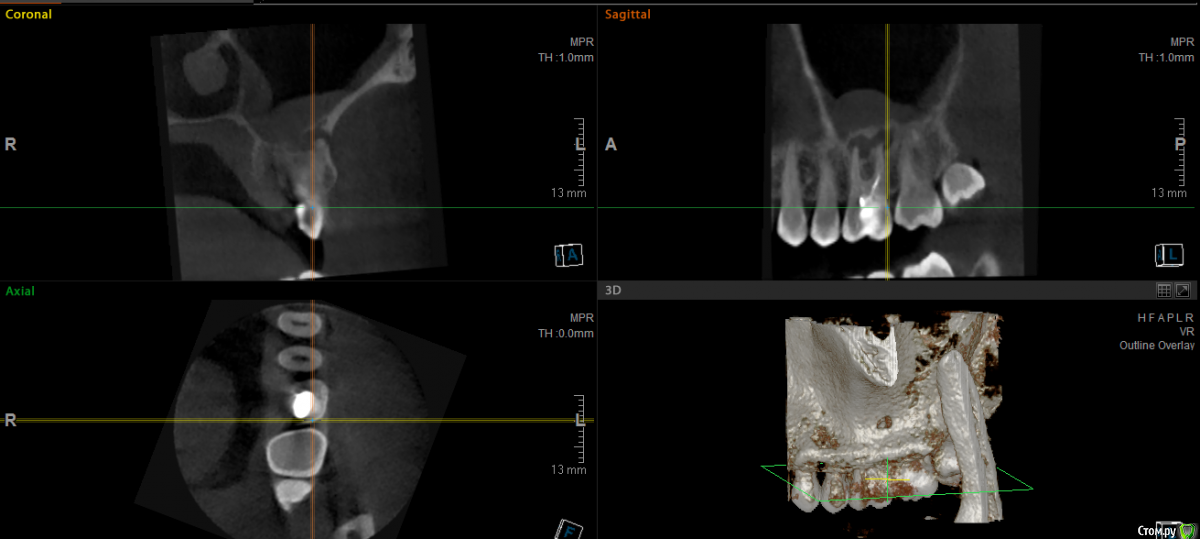

major Опубликовано 1 октября, 2015 Поделиться Опубликовано 1 октября, 2015 КТ посмотрел.Удалять, с последующей имплантацией и протезированием. Слишком глубокий скол. Ссылка на комментарий

Евгений+ Опубликовано 1 октября, 2015 Автор Поделиться Опубликовано 1 октября, 2015 (изменено) Можно несколько вопросов по имплантации: 1. Возможна ли одномоментно с удалением?2. Какая сейчас толщина кости до пазухи? (хватит для имплантата или нужно наращивать кость)3. Будет ли влиять на имплантацию гранулема/киста или сначала с ней нужно разобраться?4. С удалением нужно поторопиться или желательно что бы кто удалял тот и ставил имплант? Спасибо! Изменено 1 октября, 2015 пользователем Евгений+ Ссылка на комментарий

колесников Опубликовано 1 октября, 2015 Поделиться Опубликовано 1 октября, 2015 У вас там на 3ёх корнях по кистогранулёме и полип в пазухе. Дно пазухи перфорировано ,корни и что неприятно,корневой наполнитель контактируют с полипом. Сохранять нельзя-удалять. Обратитесь к отоларингологу,эндоскопически желательно исследовать полип. Если просто пролиферация интимы-можно удалять и ставить имплант одномоментно,если это грибковый полип-вначале удаляете зуб и полип ,а только затем решаете вопрос с пластикой. Ссылка на комментарий